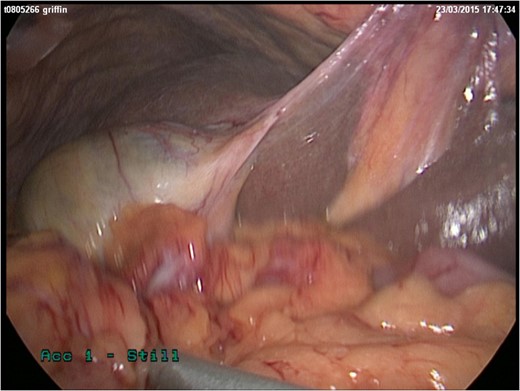

She represented later to our unit with recurrent vomiting. Her investigations revealed a raised lactate and acidosis on arterial blood gas. There was a concern for gastric ischaemia; the decision was taken to proceed to theatre. Given that she was haemodynamically stable with no peritonitis, we chose to operate using a laparoscopic approach. Surgery was performed through four laparoscopy (2 × 11 mm, 2 × 5 mm). A diagnosis of Morgagni hernia was made (Fig. 2). Inside the hernial sac was the transverse colon, the greater curvature of the stomach with a partial gastric volvulus (Fig. 3). The hernia was reduced with the viscera still viable but the sac could not be excised. The defect was repaired with a 6 × 10 cm composite mesh with an absorbable tic fixation on the diaphragm (Fig. 4). No drain was inserted, and the operation time in total was 45 minutes.